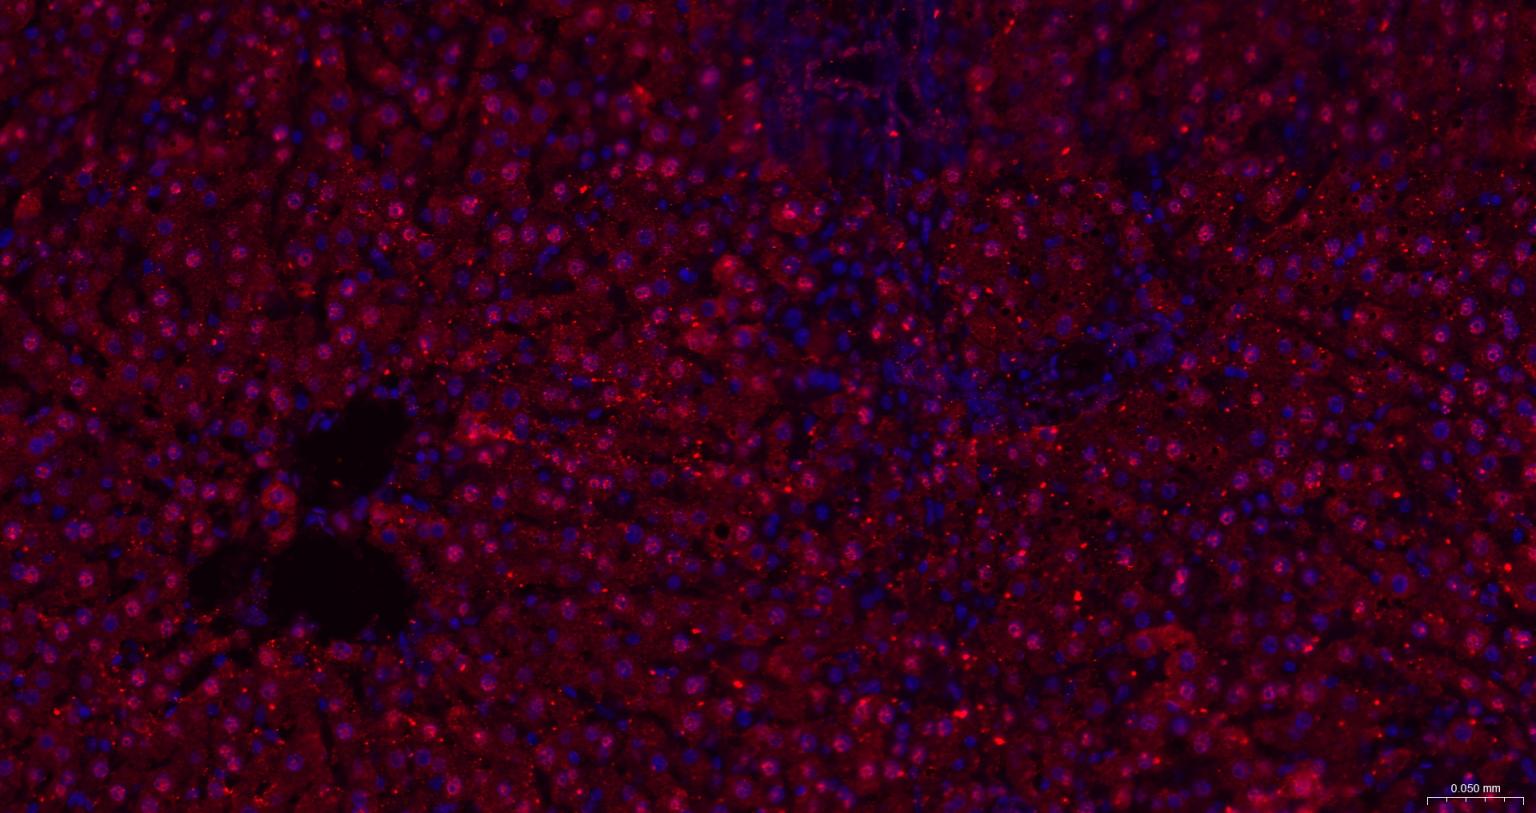

Paraformaldehyde-fixed, paraffin embedded Human Placenta; Antigen retrieval by boiling in sodium citrate buffer (pH6.0) for 15 min; The section was incubated with HDGF Monoclonal Antibody, Unconjugated (bsm-62928R) at 1:200 overnight at 4°C. Followed by conjugated Goat Anti-Rabbit IgG antibody (Red, bs-0295G-BF594), DAPI (blue, C02-04002) was used to stain the cell nuclei.